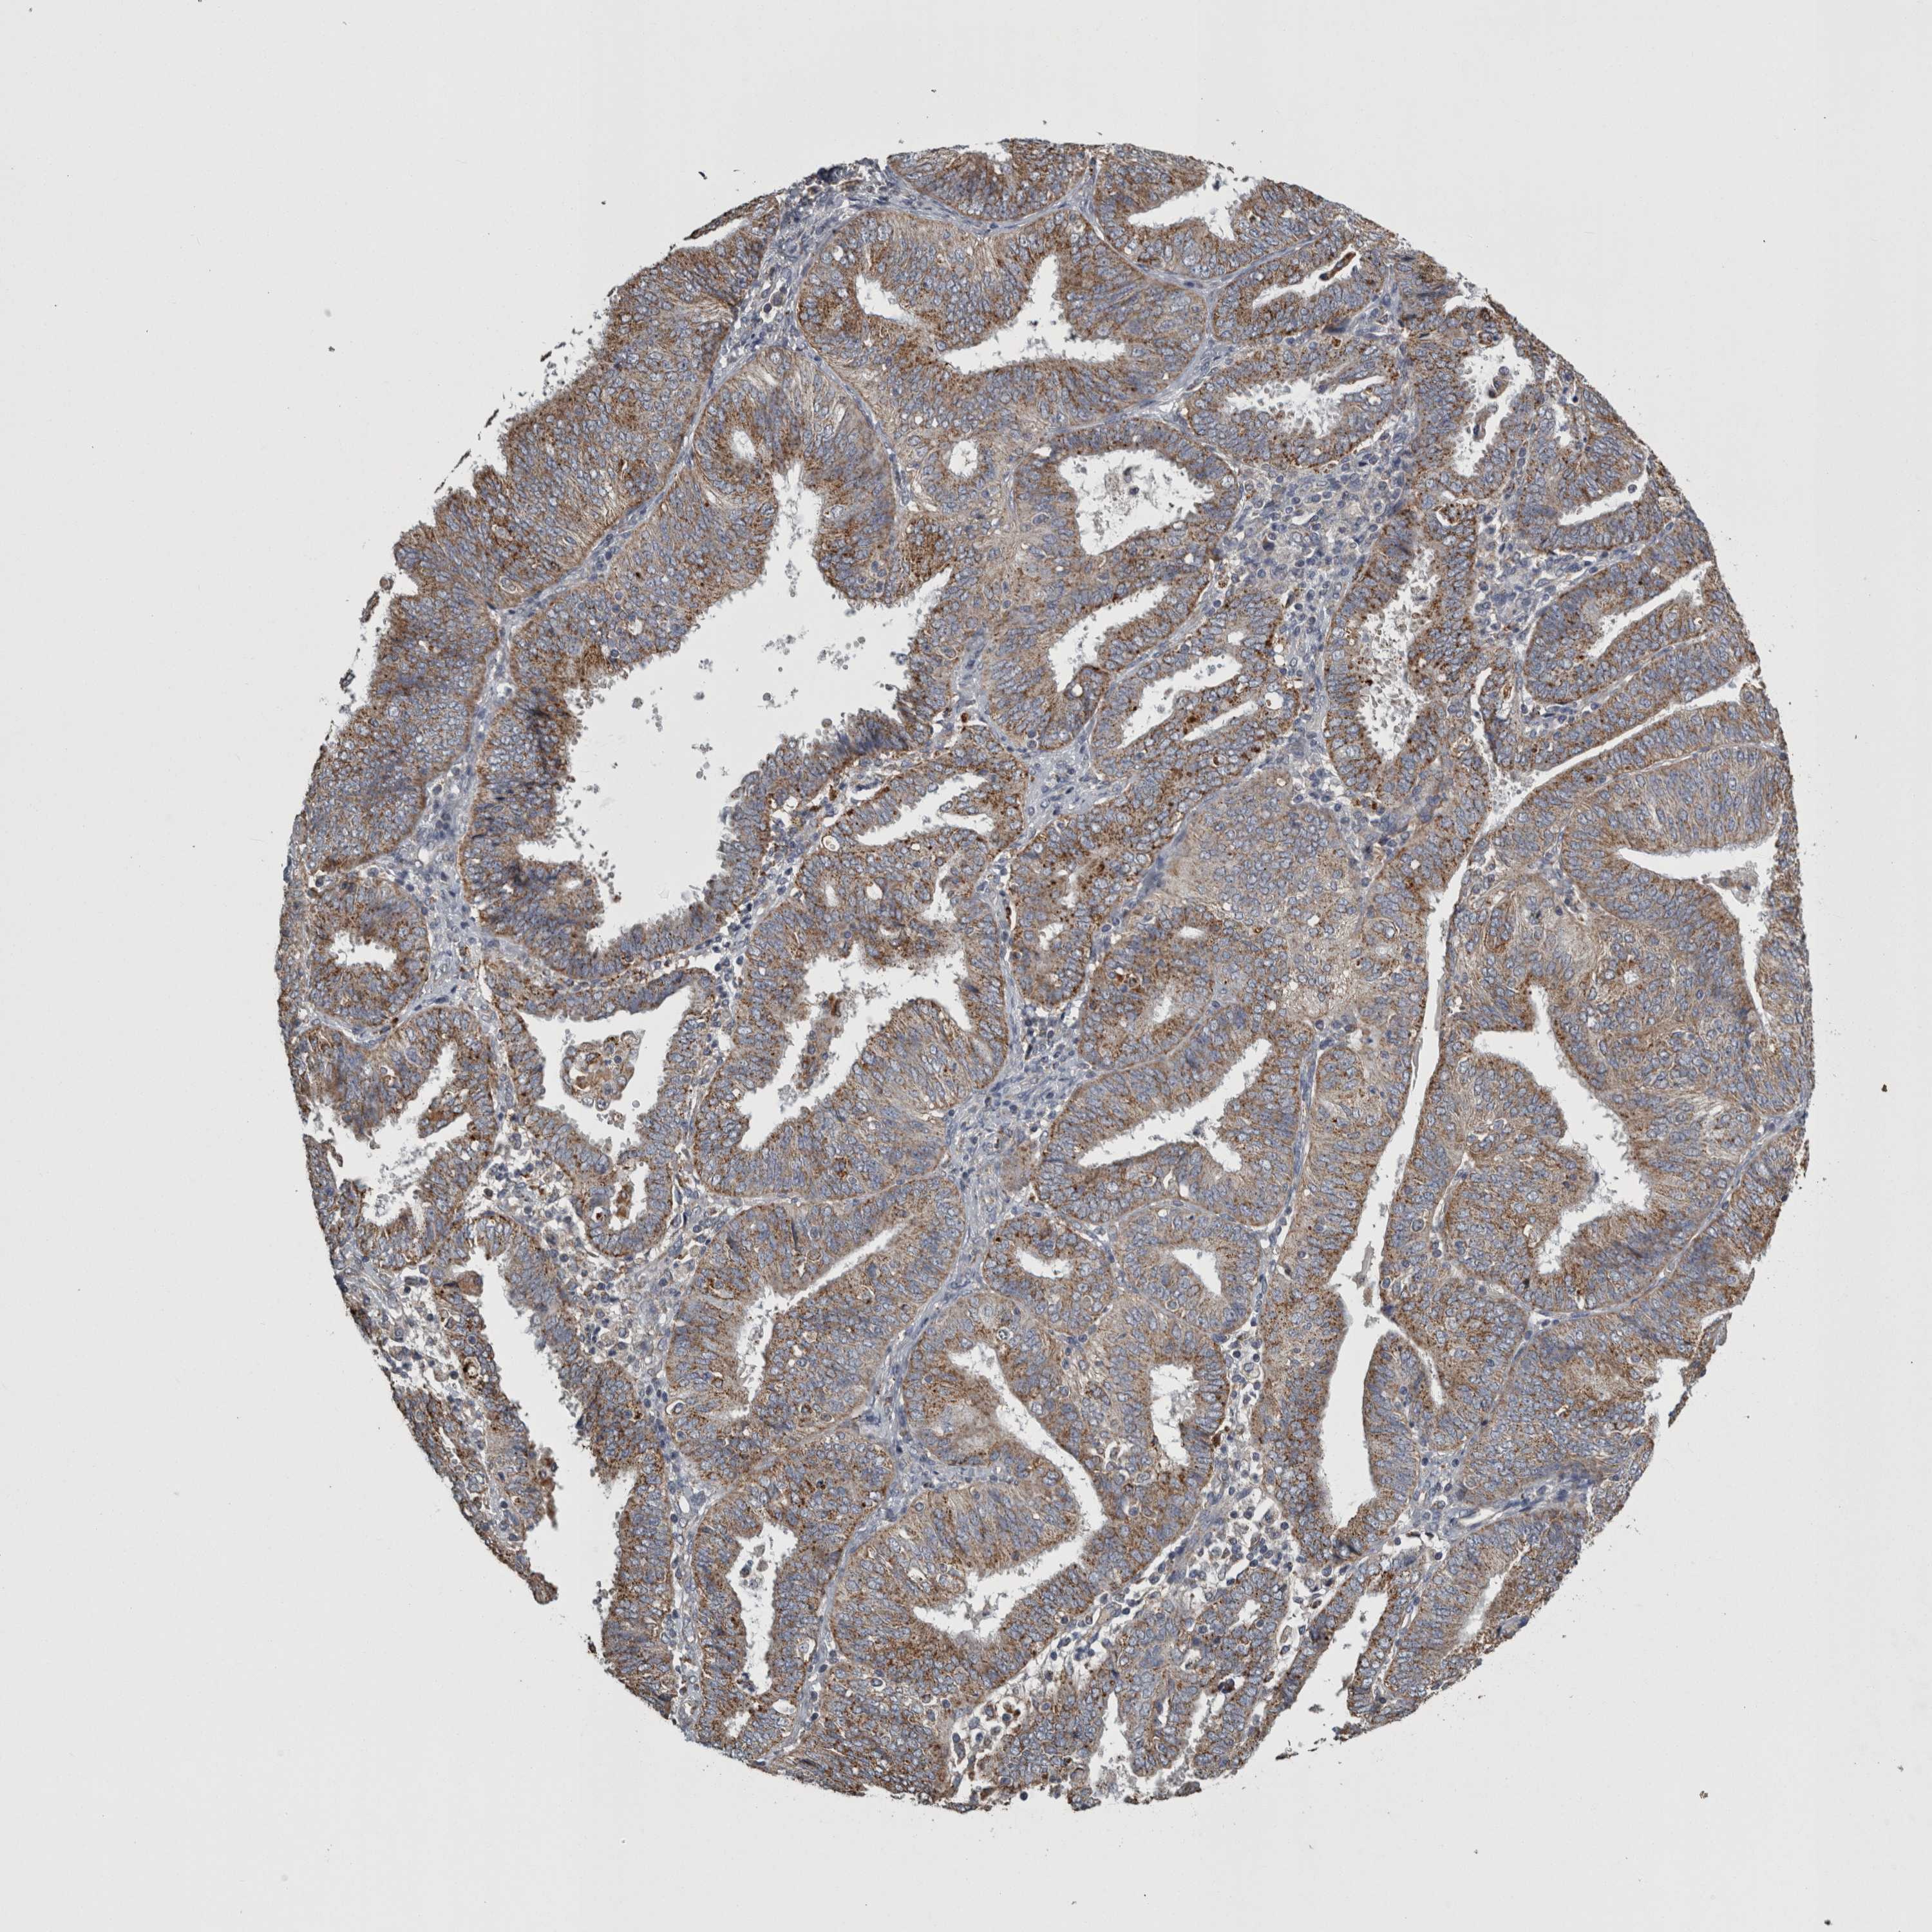

ENDOMETRIAL CANCER - Protein expressioni

A mouse-over function shows sample information and annotation data. Click on an image to view it in a full screen mode. Samples can be filtered based on level of antibody staining by selecting one or several of the following categories: high, medium, low and not detected. The assay and annotation is described here.

Note that samples used for immunohistochemistry by the Human Protein Atlas do not correspond to samples in the TCGA dataset.

Antibody stainingi

Antibody staining in the annotated cell types in the current human tissue is reported as not detected, low, medium, or high, based on conventional immunohistochemistry profiling in selected tissues. This score is based on the combination of the staining intensity and fraction of stained cells.

Each image is clickable and will lead to virtual microscopy that enables deeper exploration of all samples and also displays staining intensity scores, fraction scores and subcellular localization as well as patient and tissue information for each sample.

Antibody HPA072590

Antibody CAB025217

Staining

High

Medium

Low

Not detected

Intensity

Strong

Moderate

Weak

Negative

Quantity

>75%

75%-25%

<25%

None

Location

Nuclear

Cytoplasmic/membranous

Cytoplasmic/membranous,nuclear

Adenocarcinoma, NOS